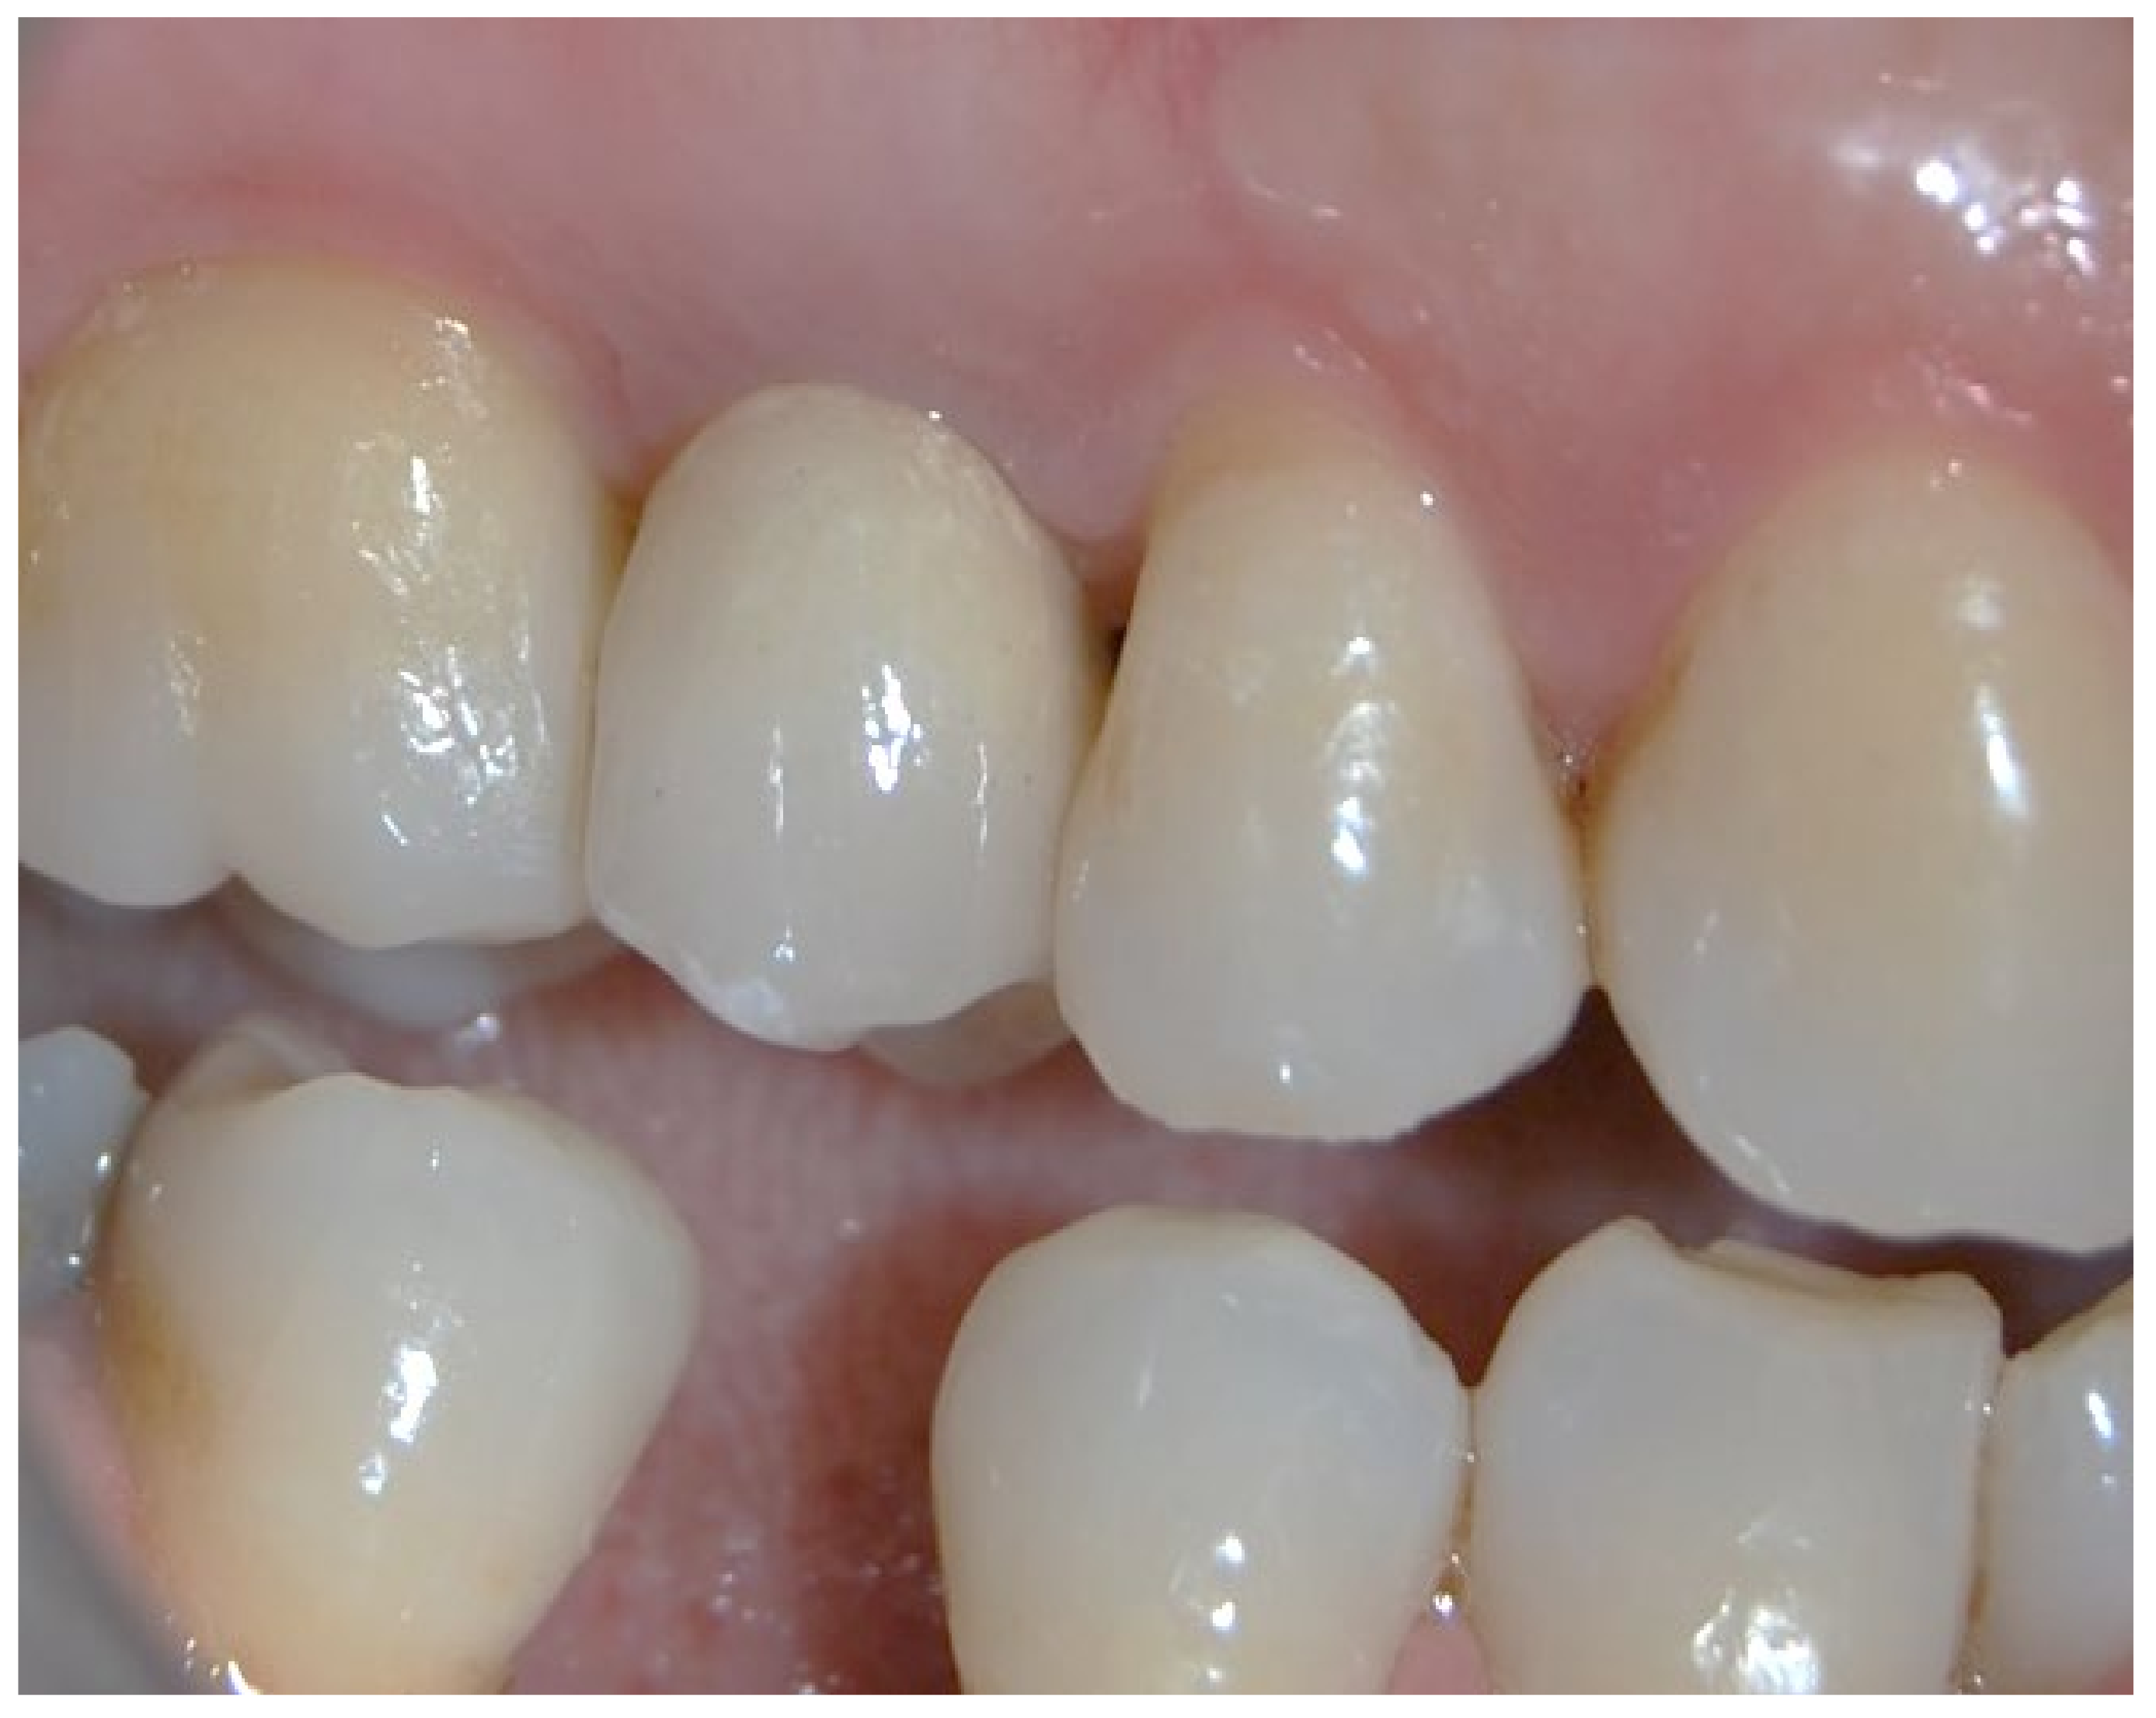

3. Results